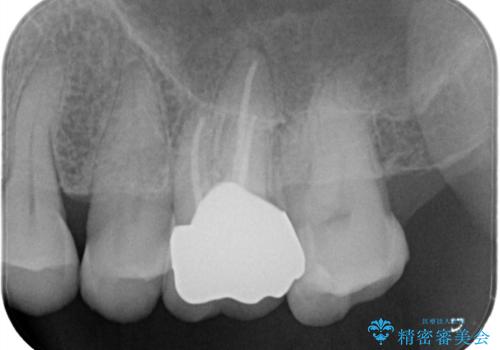

- 治療計画

- 1つ目の医院にて虫歯の治療を行い詰め物を入れたがその後、痛みを感じるようになった。2つ目の医院を受診したところ根の先に膿があるため、根の治療が必要と言われた。そこで根の治療を2回程度受けたが、毎回15分くらいで治療が終わり、痛みもとれず不安を感じたため当院に来院された患者様です。

根管治療を行ったのち、症状改善を認めオールセラミッククラウンにて修復治療を行いました。

根管治療にはラバーダムシートをつけて行うことが大切です。マイクロスコープを使用し治療を行いました。治療後、歯の痛みは消失し、とても満足していただきました。

根管治療を行った歯は、再発防止や残された歯質を守るため、クラウンによる補綴治療が必要となります。